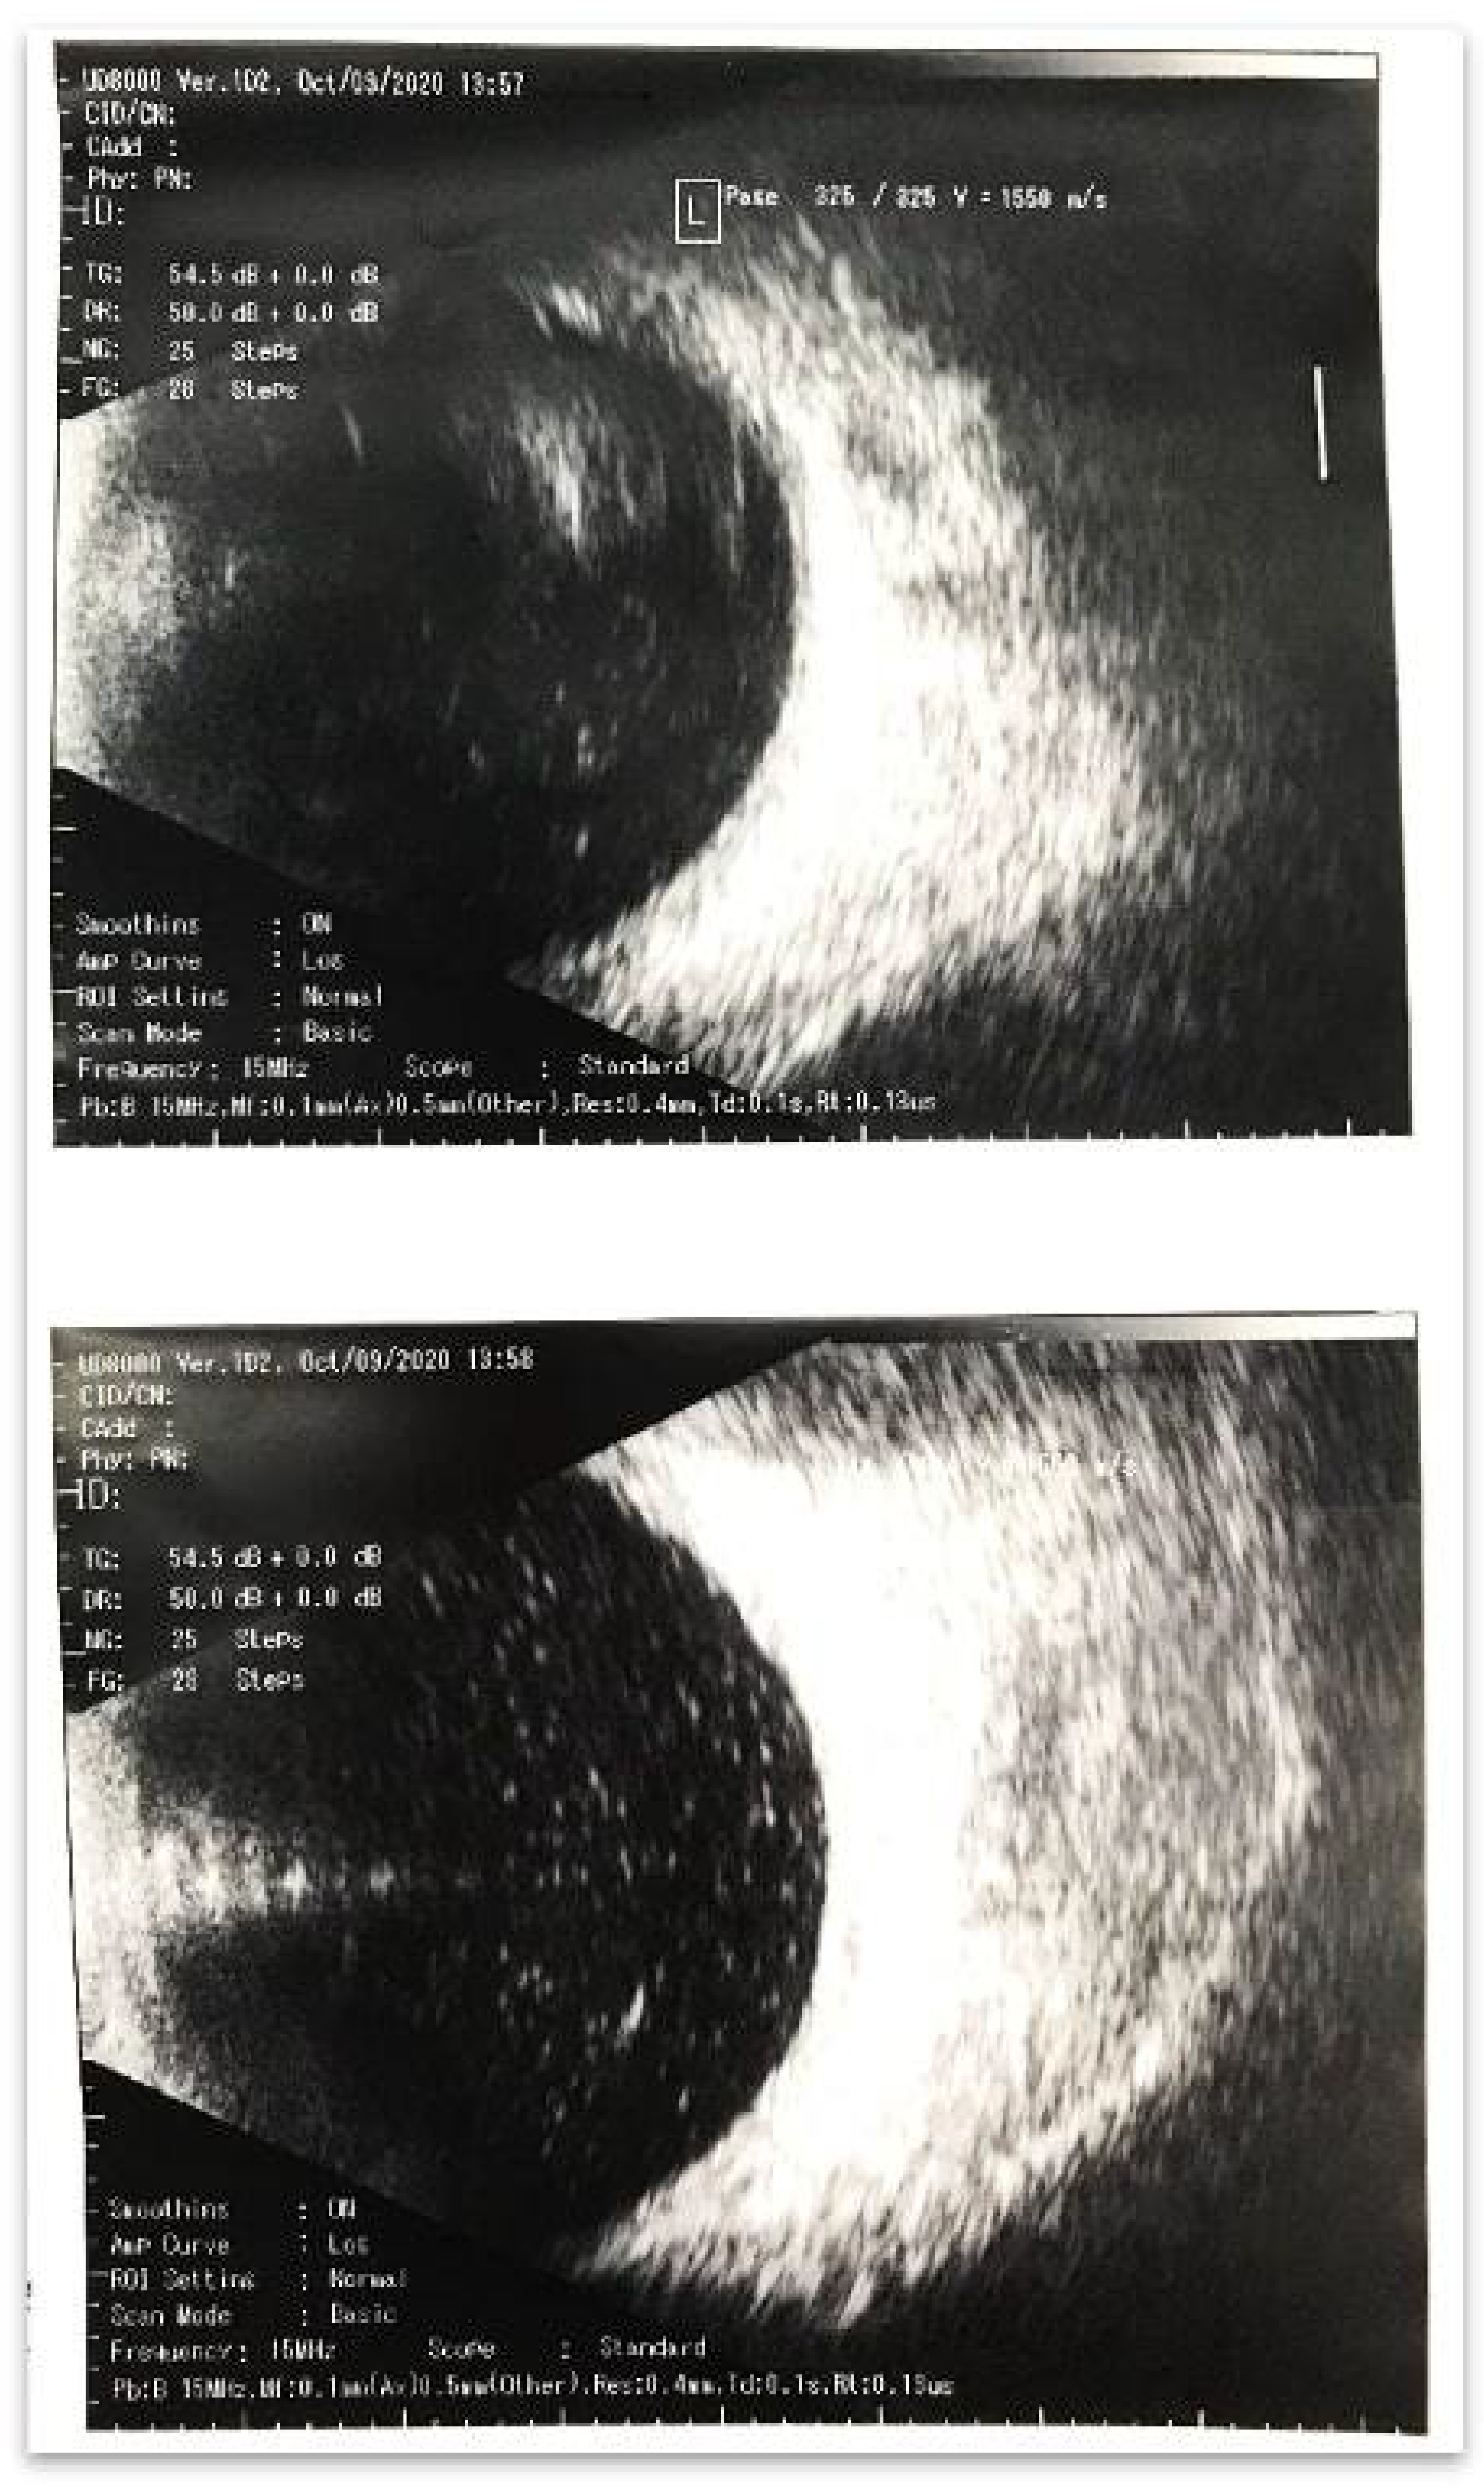

The patient complained of decreased visual acuity and pain in the operated eye on 9th October 2020 at 10.00 AM. Vis = 0.005, IOP = 14, transparent cornea, and fibrin filaments in the anterior chamber and on the IOL showed weak fundus reflex Figure 1a. The ultrasonography conducted at 10.30 AM revealed a massive hyperreflexive inflammatory suspension in the vitreous cavity (Figure 2). It should be noted that clinical manifestations appeared, such onset which is not typical for endophthalmitis, especially in the avitreal eye were observed. Endophthalmitis usually occurs within 3–7 days or more. Our findings could indicate a massive drift of the pathogen or an autoimmune reaction. In this case, the absence of hypotension may indirectly indicate tightness of access.

Figure 2. The ultrasonography conducted at 10.30 AM revealed a massive hyperreflexive inflammatory suspension in the vitreous cavity.